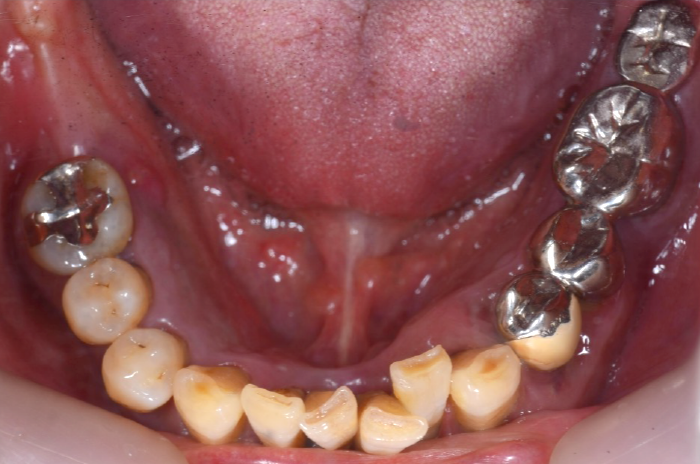

初診時の状態

歯周病により歯はグラグラの状態で、元の位置から動いてしまっていました。

また、レントゲン写真でも歯を支えている骨が吸収していることが明らかで、噛む力を十分に支えられない状態でした。

このままの状態で歯を残すことは難しく、抜歯が必要と判断しました。

初診時口腔内写真